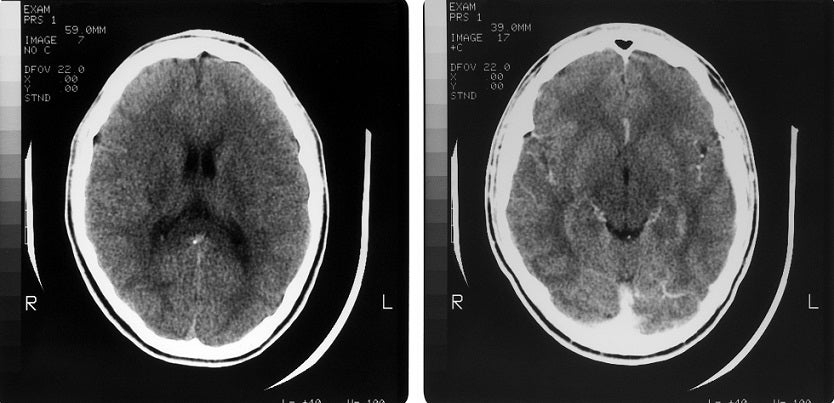

Los médicos le realizaron una tomografía computarizada, revelando la presencia de palillos dentro del cerebro del paciente.

Por su parte, los médicos le realizaron una tomografía computarizada, revelando la presencia de palillos dentro del cerebro del paciente. Además, se le diagnosticó neumoencéfalo a tensión, una afección neurológica provocada por la acumulación de aire intracraneal.

Los palillos resultaron ser la causa subyacente de esta dolencia. El doctor Nguyen Van Man explicó que estos objetos habían ingresado por la nariz del paciente, incrustándose en su cerebro.

Para aliviar los intensos dolores de cabeza, el paciente se sometió con éxito a una cirugía para extraer los palillos incrustados. Esta intervención fue crucial para prevenir futuras complicaciones derivadas de la presencia de estos objetos extraños en su cráneo.